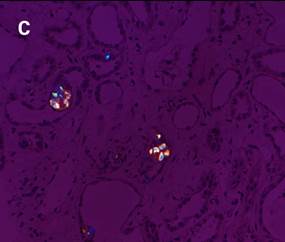

痛風診斷金標準是針吸活檢發(fā)現(xiàn)尿酸鹽結(jié)晶,尿路感染、關節(jié)病變等疾病診斷也需要觀察晶體。如圖3-a,在常規(guī)顯微鏡下很難觀察到腎臟樣本中的晶體;如圖3-b,使用偏光顯微鏡觀察時,視野組織背景全黑,草酸鹽晶體非常明顯;如圖3-c,在偏光光路中加入合適的配件,可以明顯地草酸鹽晶體分布在腎小管中。

圖3:HE染色腎臟組織切片中草酸鹽晶體檢測。